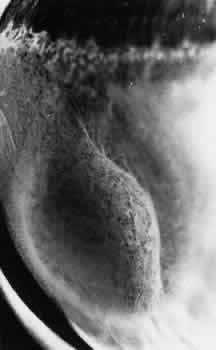

Larger than a noncystic tuft, the cystic retinal tuft is a nodular projection of retinal tissue that extends from a vitreous attachment at the apex to a base that is more than 0.1 mm in diameter and surrounded by cystic retinal degeneration (Fig. 38). Single ormultiple cystic retinal tufts may be located within or posterior to the vitreous base. On microscopic appraisal, the tuft, attached internally to a vitreous strand, is composed of degenerated and proliferated retinal cells that may contain a few pigment granules (Fig. 39). There may also be degeneration of the adjacent retinal pigment epithelium.

Fig. 38. Cystic retinal tuft in peripheral retina of a 14-year-old boy. Tuft measures 0.47 mm at its circular base, is 3.7 mm from the ora serrata, and contains many microcysts with dense walls. (× 19.)